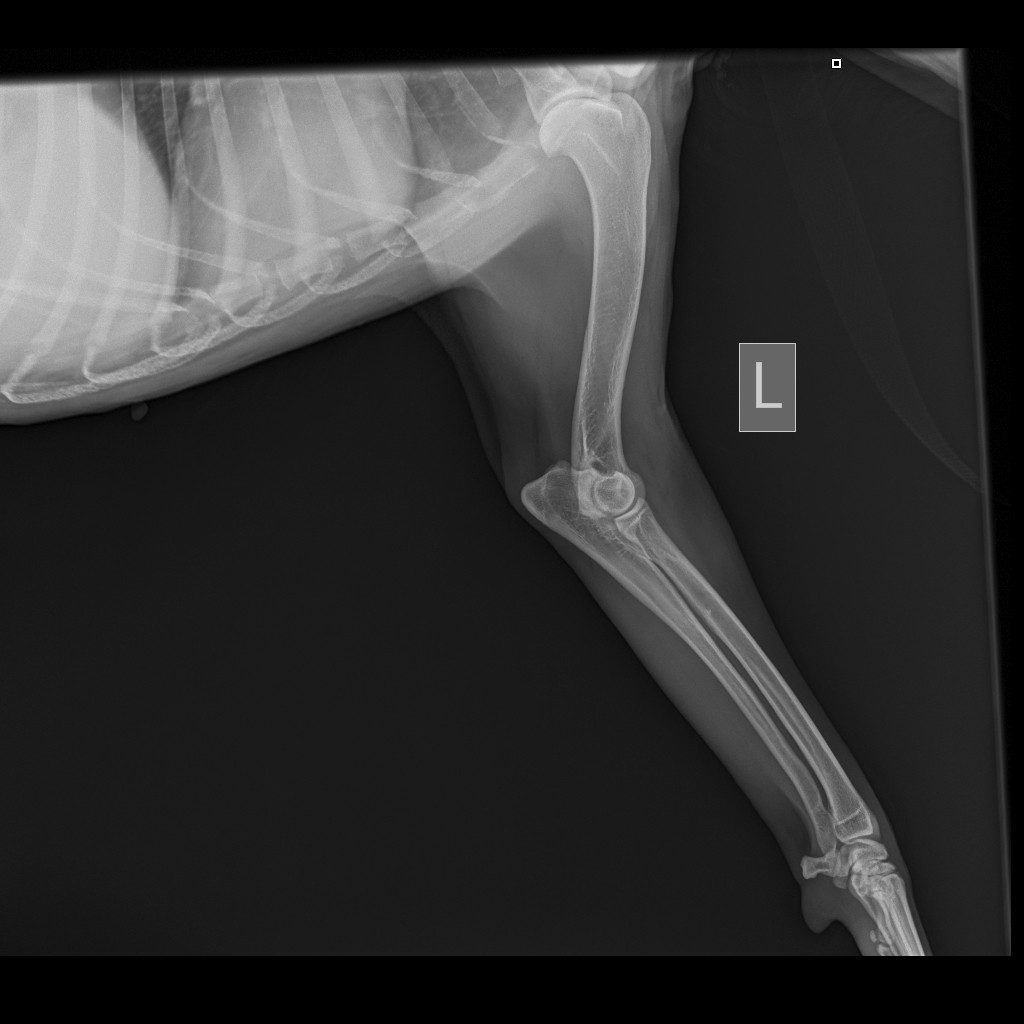

На обзорной рентгенограмме скелета левой передней конечности определяется:

Признаки мелких остеофитов на суставной поверхности запастья. Локтевой сустав без видимых изменений.

На обзорной рентгенограмме скелета правой передней конечности определяется:

Заключение: R-признаки артроза запястных суставов грудных конечностей.